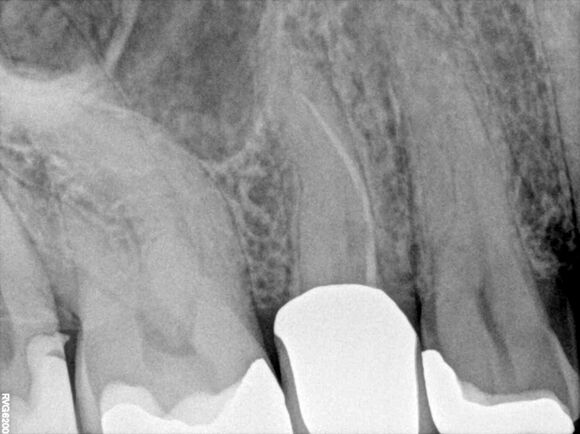

Beispiel 1: Vorher

Schwierige Krümmungen und sehr grazile Wurzeln.

Beispiel 1: Nachher

Die perfekte Wurzelfüllung!